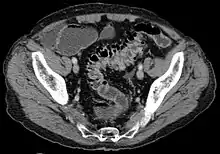

Diagnosis

Diverticulosis is defined by the presence of multiple pouches (diverticula) in the colon.[22] In people without symptoms, these are usually found incidentally during other investigations.

Imaging

- Barium enema is inferior to colonoscopy in terms of image quality and is usually only performed if the patient has strictures or an excessively tortuous sigmoid colon where colonoscopy is difficult or dangerous.

- Colonoscopy will show the diverticulum and rule out malignancy. A colonoscopy should be performed 4–6 weeks after an acute episode.

- Contrast CT is the investigation of choice in acute episodes of diverticulitis and where complications exist.